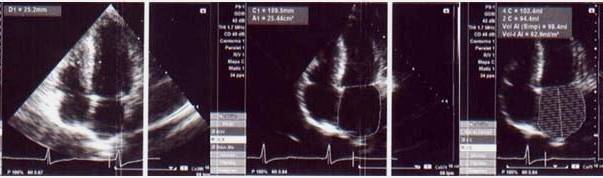

Los hallazgos del SPM son ilustrados en la fig. 4; se observa HVI severa a predominio septal, dilatación transitoria del ventrículo izquierdo (VI), fracción de eyección ventricular izquierda (FEVI) basal en el límite normal inferior (49%), con caída significativa post-esfuerzo (39%). Sin embargo, no existen defectos de perfusión de tipo segmentario.

Si bien el SPM no representa el estudio de elección en pacientes con sospecha de MCH, en nuestro caso el mismo fue de orientación diagnóstica al demostrar HVI severa a predominio septal y trastornos funcionales acompañantes. En particular, la dilatación transitoria del VI sin defectos de perfusión se ha reportado en pacientes con MCH y coronarias epicárdicas normales(11), siendo controversial si se trata de una verdadera dilatación post-isquémica o si la misma es aparente por isquemia subendocárdica difusa. De todas maneras, parece razonable considerar que existe una alteración de la reserva coronaria en estos pacientes, y que la misma se traduce como una verdadera isquemia durante el ejercicio que incluso puede explicar la caída de la FEVI. También puede interpretarse que una obstrucción dinámica severa es capaz de producir una caída de la FEVI que aumente la desproporción ya conocida entre número de vasos y masa miocárdica que tienen estos pacientes.